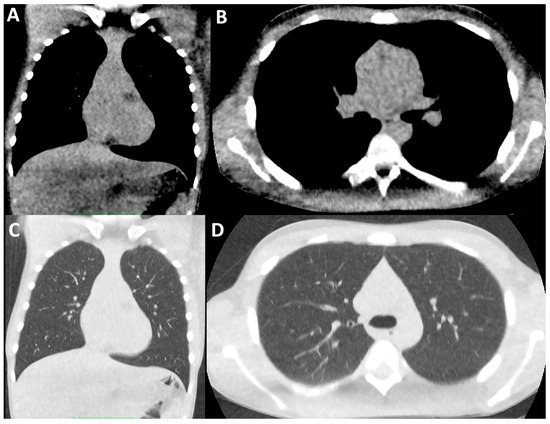

- Moloney, F.; Kavanagh, R.G.; Ronan, N.J.; Grey, T.M.; Joyce, S.; Ryan, D.J.; Moore, N.; O’Connor, O.J.; Plant, B.J.; Maher, M.M. Ultra-low-dose thoracic CT with model-based iterative reconstruction (MBIR) in cystic fibrosis patients undergoing treatment with cystic fibrosis transmembrane conductance regulators (CFTR). Clin. Radiol. 2021, 76, 393.e9–393.e17. [Google Scholar] [CrossRef] [PubMed]